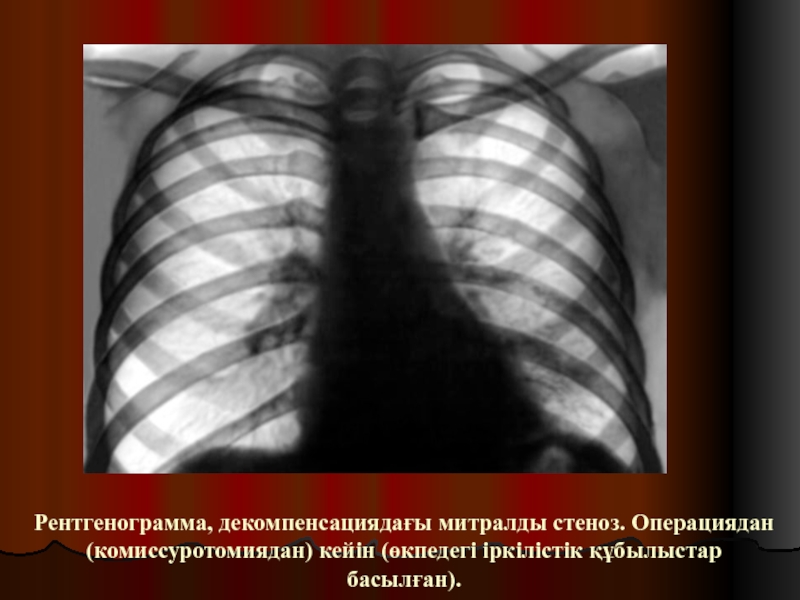

Слайд 33Рентгенограмма, декомпенсациядағы митралды стеноз. Операциядан (комиссуротомиядан) кейін (өкпедегі іркілістік құбылыстар

басылған).

Рентгенограмма, декомпенсациядағы митралды стеноз. Операциядан (комиссуротомиядан) кейін (өкпедегі іркілістік құбылыстар басылған).